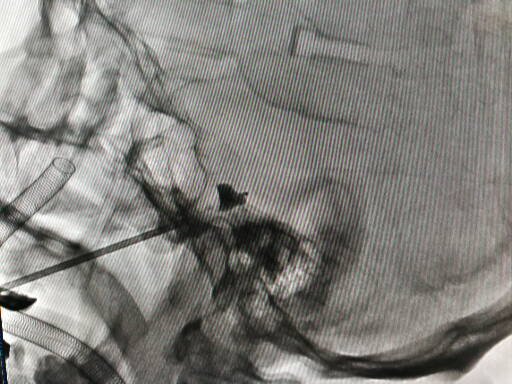

入院后經詳細詢問病史以及對病側三叉神經的痛覺、觸覺及運動等進行詳細評估,同時結合患者年近八旬、心肺功能差、營養(yǎng)狀況不良等因素,神經外科治療小組為患者實施了“三叉神經半月節(jié)微球囊壓迫術”。僅僅通過在病側口角外側約2.0cm皮膚穿刺,一次性成功將“微球囊”精準置入到位,微球囊壓迫半月節(jié)約3分鐘,撤出球囊及穿刺針,整個過程不超過十分鐘。術后困擾患者16年的疼痛消失了,使患者的臉上又有了笑容。

2.“微球囊”壓迫技術:是在影像引導下通過“微球囊”對三叉神經半月神經節(jié)進行短暫壓迫,從而阻斷痛覺神經傳導,最終達到祛除疼痛的治療效果。整個過程采用短暫舒適麻醉,不僅避免了局麻半月神經節(jié)射頻熱凝術所帶來的劇烈疼痛及相關風險,更無需開顱。微創(chuàng)不開顱、舒適無痛苦、手術時間短、風險相對較低。